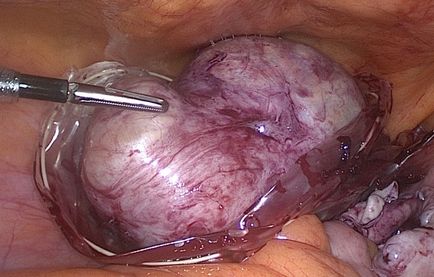

Доброкачествените тумори кистозна природата, които засягат тъкан може да бъде от няколко вида и имат специфични характеристики. Сред всички заболявания, които засягат яйчниците отделят чужди тела доброкачествени и злокачествени характер. За да oothecoma възпалено жена може да се изправи и в двата случая.

Заболявания или доброкачествени кисти се появяват за предпочитане от неексплодирали фоликул или жълтото тяло и в повечето случаи независимо резорбират по време на менструация. Въпреки това, ако пациентът изпитва болка, когато овариални кисти, и капсулата че засегнати тъканта на тялото е оформен от патологични тъкани, и не е морфологична част на репродуктивната система, растеж и патогенния ефект на отрицателно въздействие върху функционирането на женската репродуктивна система, да доведе до възпаление, инфекция, и развитие безплодие.

Такива тумори често при рутинна диагностика или вече са в късните етапи на развитие, когато единственият начин за лечение е хирургично отстраняване и почистване на организма. модели на растеж, нисш коремна болка със симптоми овариални кисти и образуване на анормален зависи от много фактори. Първият от тях е:

Как боли киста на яйчника? Циститна тялото, които са разположени в репродуктивните органи и растат в големи размери, един или друг начин, в зависимост от тяхната прогресия оказване на натиск върху съседни органи и репродуктивна система или естеството на стомашно-чревния тракт. Поради тази причина, най-често срещаните и очевиден симптом на заболяването са заядлив и тъпа болка в кисти на яйчниците симптоми са долната част на корема или около пъпа.

Къде Ви боли киста на яйчниците? Голям кистозна тяло не само да повлияе на яйчниците тъкан. Те са изключително опасни и патогенни за съседни органи и системи. Защо болка киста на яйчниците? По този начин, кисти по-голям от 10 см натискат надолу мехур. По този начин аномалия провокира болка при уриниране, чувство за стягане в областта на таза.

В допълнение към болката заболяването се проявява в развитието на разширена корема. Това се случва, поради причината, че капсула ненормално тяло постепенно се разраства и започва да натиснете съседните органи и системи. Поради тази последна възпалена, представят слабо, или болки в корема по време на киста на яйчниците. В рак на яйчниците пациенти често се чувстват: болка при уриниране, дискомфорт след хранене, стомашно разстройство и болка в червата. Неотдавна, доказателство за лошо храносмилане, и проблеми с храносмилателния тракт.